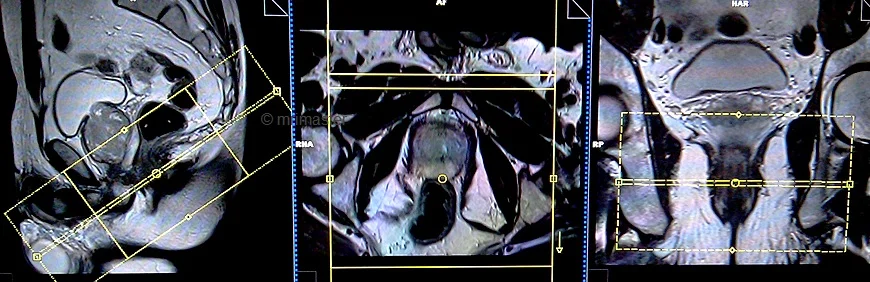

T2 tse axial oblique 3mm SFOV pre proctogram

Plan the axial oblique slices on the sagittal plane; angle the positioning block perpendicular to the anal canal. Check the positioning block in the other two planes. An appropriate angle must be given in the coronal plane (perpendicular to the anal canal). Slices must be sufficient to cover the entire anal canal.

TR 4000-5000 | TE 100-120 | SLICE 3 MM | FLIP 130-150 | PHASE A>P | MATRIX 320X320 | FOV 180-230 | GAP 10% | NEX(AVRAGE) 4 |

T2 tse coronal oblique 3mm SFOV pre proctogram

Plan the coronal oblique slices on the sagittal plane; angle the positioning block parallel to the anal canal. Check the positioning block in the other two planes. An appropriate angle must be given in the axial plane (horizontally across the anal canal or parallel to the right and left hip joint). Slices must be sufficient to cover the whole anal canal.

TR 3000-4000 | TE 100-120 | SLICE 3 MM | FLIP 130-150 | PHASE R>L | MATRIX 320X256 | FOV 180-230 | GAP 10% | NEX(AVRAGE) 5 |